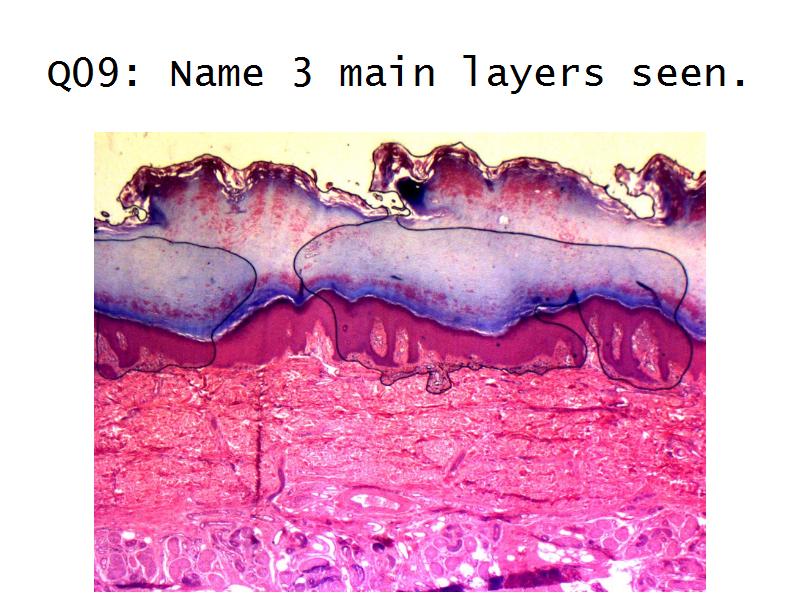

Kidney

Oral Cavity

Kidney

Slides 28 & 76

Kidney: Objectives

- Basic anatomy of the kidney

- Basic arrangement of nephrons and collecting tubules in the kidney

- Structure of the nephron and collecting tubules

- The renal corpuscle